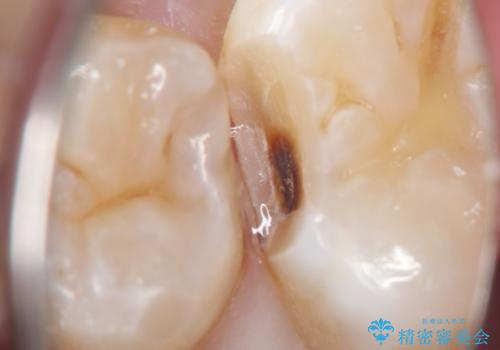

- 定期検診にて虫歯が見つかった患者様です。

金属のインレーの下と、歯と歯の間も虫歯だったため、つなげた形でセラミックインレーにて修復を行なっています。

e-max プレスインレーを用いることで、適合の良い治療ができます。